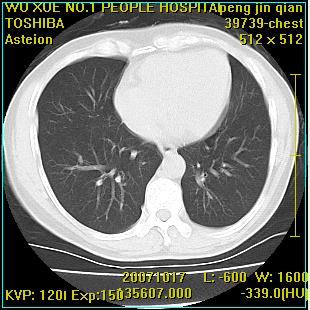

标题: CT10148:男,56岁,咳血。 [打印本页]

标题: CT10148:男,56岁,咳血。

左肺上叶尖后段较大团块影,边缘光滑,内见不规则裂隙样空洞,周围明显见细小结节及渗出,与肺门方向结构紊乱,另:左上叶尖段外侧 舌叶内侧 右上叶尖段及下叶背段均见片状致密影。考虑:继发性肺结核伴空洞形成!

左肺上叶尖后段较大团块影,边缘光滑,内见不规则裂隙样空洞,周围明显见细小结节及渗出,与肺门方向结构紊乱,另:左上叶尖段外侧 舌叶内侧 右上叶尖段及下叶背段均见片状致密影。考虑:继发性肺结核伴空洞形成!建议进一步检查,除外肺癌

以下是引用卜一在2007-10-22 16:36:00的发言:[br]左肺上叶尖后段较大团块影,边缘光滑,内见不规则裂隙样空洞,周围明显见细小结节及渗出,与肺门方向结构紊乱,另:左上叶尖段外侧 舌叶内侧 右上叶尖段及下叶背段均见片状致密影。上腔静脉后淋巴结肿大,内有钙化。考虑:继发性肺结核伴空洞形成!

浸润型肺结核伴左上肺空洞形成,两肺播散灶